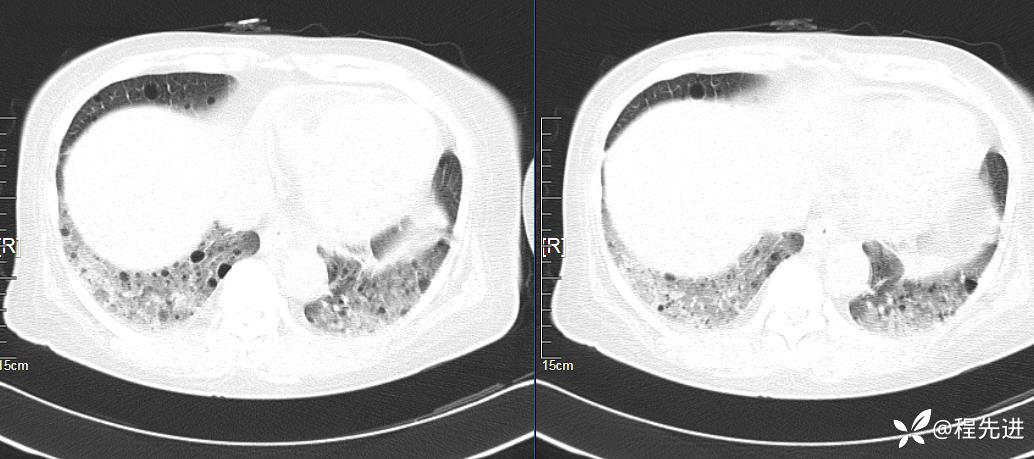

简要病史:胸闷、气促、进行性呼吸困难5年,双下肢浮肿、恶心呕吐1周

CT平扫(纵隔窗无特殊,就不上传了):

1、两肺弥漫性肺气囊的鉴别诊断有哪些?

2、本例肺气囊分布有什么特点?肺气囊有无小叶核心?有没有间质纤维化及伴发结节?